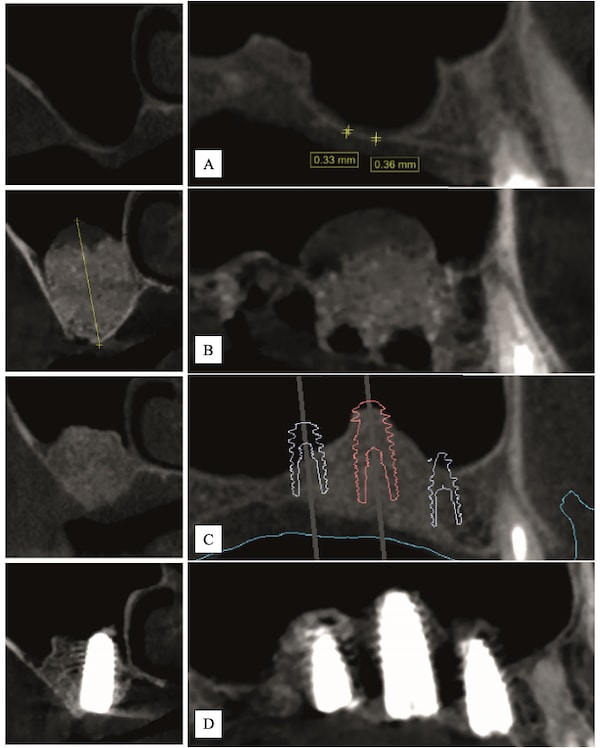

Case 1 (Figure 3 through Figure 24) depicts a 3-year follow-up of combined osseodensification sinus protocol IV in a severely resorbed maxillary ridge with ≤0.5 mm bone height in molar sites and horizontal deficiency at the first premolar site, using a two-stage approach for implant placement.

Case 2 (Figure 25 through Figure 36) illustrates a 3-year follow-up of the osseodensification sinus protocol IV in a severely resorbed right maxillary ridge with <0.5 mm bone height in molar sites, using a two-stage approach for implant placement.

Case 3 (Figure 37 through 44) shows a case of significant trauma history with a 3-year follow-up of the osseodensification sinus protocol IV in a severely resorbed right maxillary ridge with ≤0.5 mm bone height in molar sites, using a two-stage approach for implant placement.

In the posterior maxilla, bone volume, height, and density are often insufficient for implant placement and rehabilitation, which can affect implant long-term stability and success. These anatomical limitations may dictate the need for sinus grafting procedures. Osseodensification is an implant site instrumentation method that enhances bone density and can also be used for transcrestal maxillary sinus augmentation. This technique utilizes bone plasticity through specially designed burs that compact and densify bone along the osteotomy walls while simultaneously propelling bone particles laterally and apically. This process generates a hydrodynamic compaction wave at the bur tip, which propels irrigation fluid into the sinus cavity lifting the membrane and simultaneously compacting bone particles grafting the sinus with autogenous bone. Additionally, the flutes of the osseodensification bur permit the operator to subsequently graft biomaterial, facilitating further elevation of the Schneiderian membrane. Current literature outlines three specific protocols for sinus floor elevation and implant placement utilizing osseodensification with residual bone height (RBH) requirements: ≥6 mm for protocol I, ≥4–5 mm for protocol II, or ≥2–3 mm for protocol III, with concurrent implant placement in the presence of adequate bone and soft-tissue volume. Osseodensification-mediated sinus grafting allows for shorter surgery duration, reduced postoperative edema, less reported pain, and subsequently decreased analgesic intake compared to lateral window techniques. This article details the step-by-step osseodensification sinus lift protocol IV, a two-stage sinus floor elevation indicated in cases of RBH ≤0.5–1.5 mm as an alternative to lateral window techniques.

The ability of the osseodensification process to elevate the sinus floor without perforating the membrane relies on the CCW action of the densifying burs. This motion enhances irrigation throughout the osteotomy, maintaining fluid presence at the instrument tip. As a result, once the sinus floor is engaged, the irrigation and autogenous bone chips create a hydraulic wave that gently separates and lifts the sinus membrane off the bony bed and, simultaneously, autografting bone.28 Osseodensification has been documented with long-term data as safe and predictable for sinus elevation in cases with limited residual bone height.28-30 The reported minimum bone height required remains unclear in the current literature.30,31 Multicenter clinical studies confirmed the predictable outcome of osseodensification for transcrestal sinus floor elevation, even in cases with low crestal bone height, with a low rate of membrane perforation. Severe posterior maxillary bone loss, however, was identified as a risk factor for higher perforation rates.32 While these findings offer important data for clinical practice, further evidence is needed to evaluate the long-term outcomes of implants placed in sinus-augmented sites with <2 mm crestal bone height using this transcrestal osseodensification protocol.

Step 4: Allow 4 to 6 months for the sinus graft healing. CBCT evaluation is needed to evaluate the available regenerated bone height for the implant placement. Reflect soft tissue utilizing standard surgical instruments, and use Densah burs for osseodensification site preparation to prepare the implant osteotomy and place the implant.